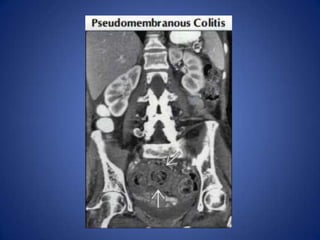

Pseudomembranous or Infectious

Colitis

• Usually diffuse, pancolonic with impressive

colonic wall thickening ("accordion sign")

• May be segmental, including distal colon

• Very common, especially in hospitalized

patients, and those in nursing homes

Pseudomembranous or Infectious Colitis •Usually diffuse, pancolonic with impressive colonic wall thickening ("accordion sign") • May be segmental, including distal colon • Very common, especially in hospitalized patients, and those in nursing homes